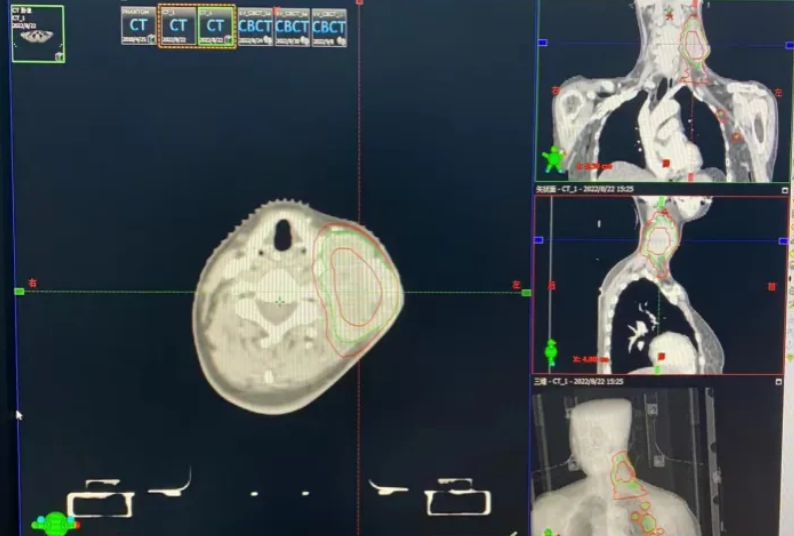

2022年8月24日开始针对转移淋巴结行同步放化疗联合卡瑞利珠单抗治疗。姑息放疗:影像可见的左颈部及腋窝多发转移淋巴结为GTV,外放0.5cm为PGTV,95%PGTV:60Gy/30F/6w,左颈部Ⅱ、Ⅲ、Ⅳ、Ⅴ区淋巴结引流区为CTV,外放0.5cm为PCTV,95%PCTV:51Gy/30F/6w。放疗期间于2022年8月25日、2022年9月16日予“卡瑞利珠单抗 200mg d1/Q21D+白蛋白结合型紫杉醇 400mg d1+奈达铂

图8 放疗计划图(2022-8-23)